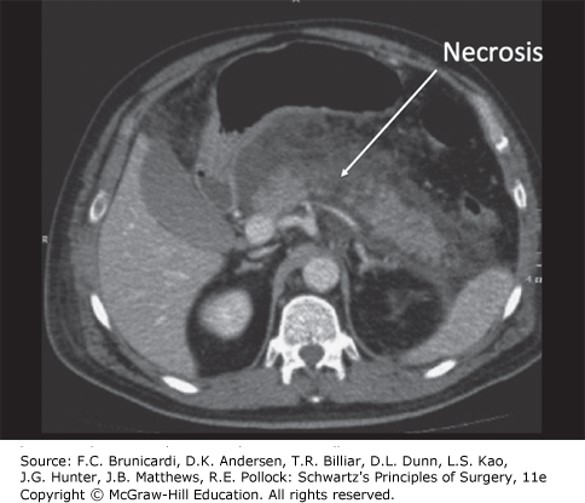

Computed tomography scan showing well perfused interstitial edematous acute pancreatitis of the neck and tail of the pancreas with a confluent area of necrosis of the pancreatic body. The pancreas is surrounded by fluid, inflammation, and possible peripancreatic fat necrosis.